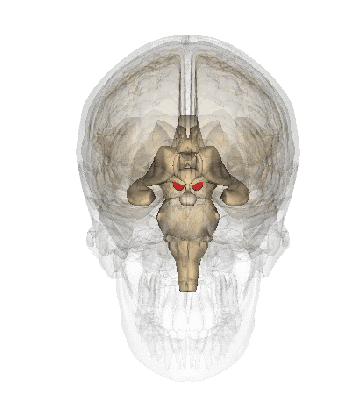

1.脑干